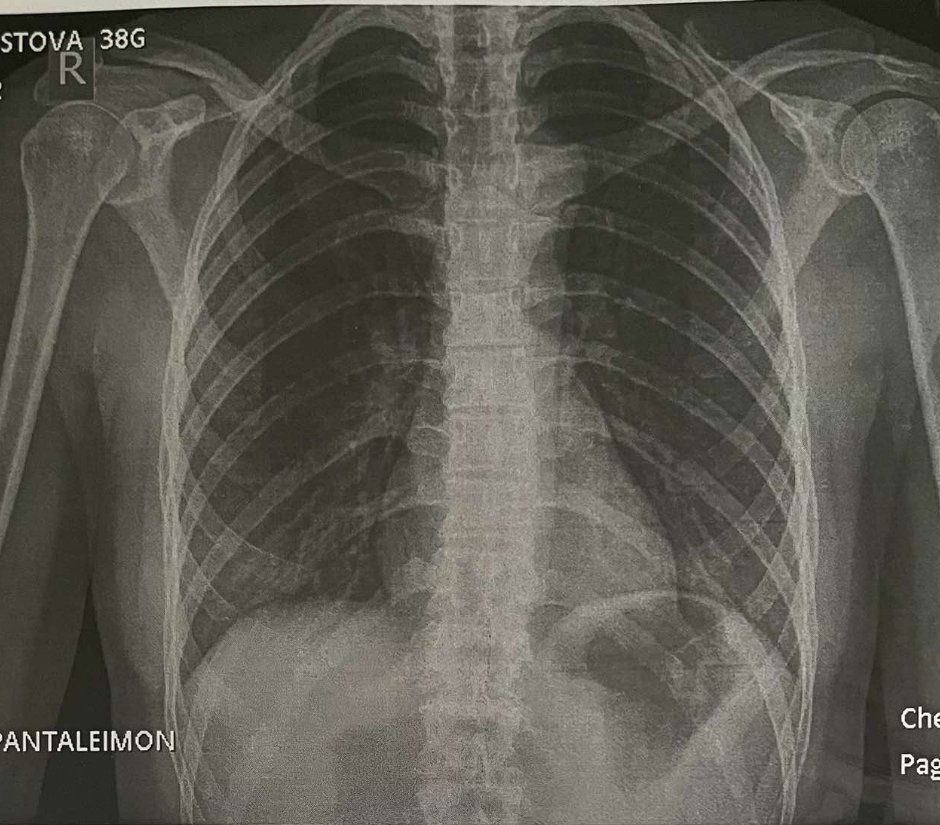

Къде мога да направя рентгенова снимка?